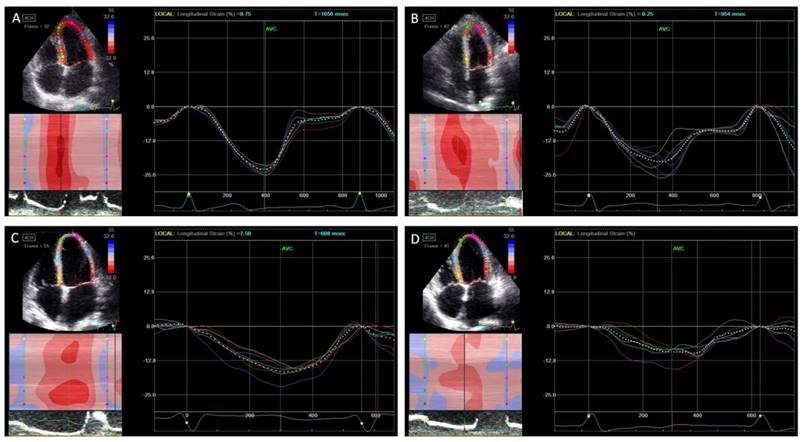

The LV function and dyssynchrony values are summarized in Table 3. The LV global LS, LSrS, and LSrE values were significantly decreased in patients with HFpEF than in normal controls and asymptomatic LVDD patients, which were even more decreased in HFrEF patients (p<0.05). However, there was no difference in global LS and LSrS values in asymptomatic LVDD patients compared to normal controls. Although Te-SD and Ts-SD were significantly more prolonged in the HFpEF and the HFrEF groups than in the control group (p<0.05), however, Ts-SD was shorter in the HFpEF group than the HFrEF group (Figure 1).

Figure 1

Peak systolic longitudinal strain and dyssynchrony. In normal controls (A), asymptomatic left ventricular diastolic dysfunction (LVDD) patients (B), heart failure with preserved ejection fraction (HFpEF) patients (C), and heart failure with reduced ejection fraction (HFrEF) (D). The peak longitudinal strain was decreased gradually from each group while the systolic dyssynchrony was increased.